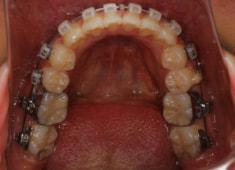

治療後(2年後)